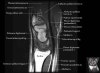

손목 관절의 MRI 단면 영상

- Sagittal section

Sagittal T1 evaluates the tendons, bone marrow and relationships between the osseous structures.